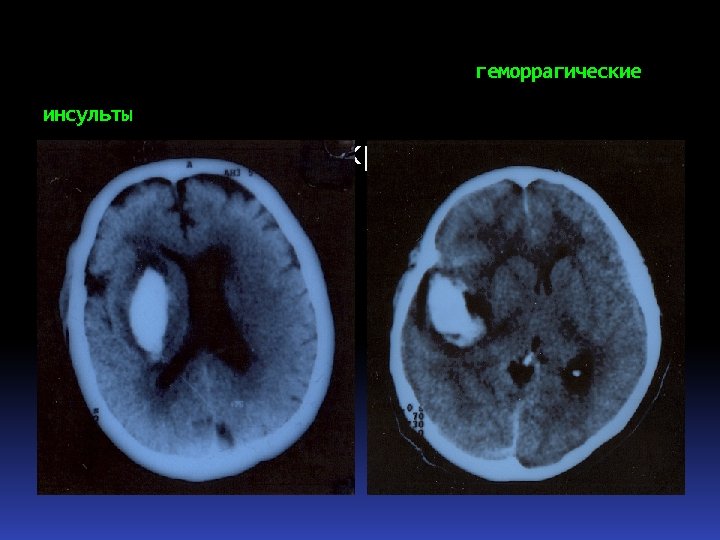

ГЕМОРРАГИЧЕСКИЙ ИНСУЛЬТ hemorrhagical s. Кровоизлияние в мозг (50 -60%) - обусловлено гипертонической болезнью или симптоматической артериальной гипертензией. Hemorrhagia in brain 50 -60% caused by hypertonic diseases

ГЕМОРРАГИЧЕСКИЙ ИНСУЛЬТ hemorrhagical s. Кровоизлияние в мозг (50 -60%) - обусловлено гипертонической болезнью или симптоматической артериальной гипертензией. Hemorrhagia in brain 50 -60% caused by hypertonic diseases

ГЕМОРРАГИЧЕСКИЕ ИНСУЛЬТЫ hemorrhagical s. Паренхиматозные (латеральные и медиаль-ные) субарахноидальные желудочковые паренхиматозно-субарахноидальные паренхиматозно-желудочковые Субдуральные Parenchomatous Subarachnoidal Ventricular Subdural

ГЕМОРРАГИЧЕСКИЕ ИНСУЛЬТЫ hemorrhagical s. Паренхиматозные (латеральные и медиаль-ные) субарахноидальные желудочковые паренхиматозно-субарахноидальные паренхиматозно-желудочковые Субдуральные Parenchomatous Subarachnoidal Ventricular Subdural

Патоморфология геморрагических инсультов Кровоизлияния по типу гематомы – кровоизлияния, образованием сопровождающиеся полости, содержащей жидкую кровь или кровяные сгустки, составляют основную геморрагических инсультов (85%). массу

Патоморфология геморрагических инсультов Кровоизлияния по типу гематомы – кровоизлияния, образованием сопровождающиеся полости, содержащей жидкую кровь или кровяные сгустки, составляют основную геморрагических инсультов (85%). массу

Наиболее частая локализация гематом: Localizations стриопаллидарная область (40%) область внутренней капсулы (16%) область зрительного бугра (10%) мозжечок (6 -10%). Striopallidar region 40% Inner capsule 16% Okular tumor area 10% Cerebellum 6 -10%

Наиболее частая локализация гематом: Localizations стриопаллидарная область (40%) область внутренней капсулы (16%) область зрительного бугра (10%) мозжечок (6 -10%). Striopallidar region 40% Inner capsule 16% Okular tumor area 10% Cerebellum 6 -10%

Острое нарушение кровоснабжения головного мозга Acute disturbance of brain blood circulation Геморрагический Ишемический

Острое нарушение кровоснабжения головного мозга Acute disturbance of brain blood circulation Геморрагический Ишемический

Пат. анатомическая картина геморрагического инсульта

Пат. анатомическая картина геморрагического инсульта